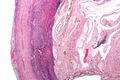

Even for clinically certain appendicitis, routine histopathology examination of appendectomy specimens is of value for identifying unsuspected pathologies requiring further postoperative management.[69] Notably, appendix cancer is found incidentally in about 1% of appendectomy specimens.[70]

Pathology diagnosis of appendicitis can be made by detecting a neutrophilic infiltrate of the muscularis propria.

Periappendicitis (inflammation of tissues around the appendix) is often found in conjunction with other abdominal pathology.[71]

Micrograph of appendicitis and periappendicitis. H&E stain

Micrograph of appendicitis showing neutrophils in the muscularis propria. H&E stain

Acute suppurative appendicitis with perforation (at right). H&E stain